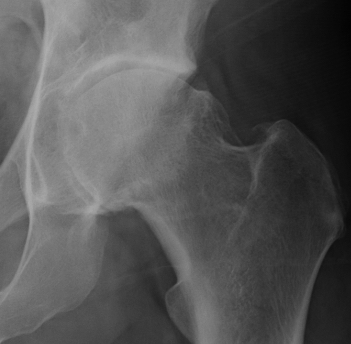

X-ray

True AP

Coccyx and symphysis pubis within 1-2cm of each other

- exclude osteoarthritis

- pincer

- dysplasia

- retroversion / crossover sign

- os acetabuli / ossification labrum

- bony prominence junction anterolateral head and neck - Cam

Osteoarthritis

Tonnis Grade

| Grade 0 | No sign of arthritis |

| Grade 1 | Sclerosis, slight narrowing of joint space |

| Grade 2 | Cyst, moderate narrowing of joint space, loss sphericity of femoral head |

| Grade 3 | Severe narrowing or obliteration of joint space |

Tonnis grade 0 Tonnis grade 1 Tonnis grade 1